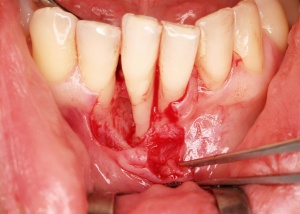

Aufgrund der fortgeschrittenen parodontalen Destruktion waren bei dem Patienten an einzelnen Parodontien weiterführende parodontalchirurgische Maßnahmen im Sinne von Lappenoperationen indiziert. Die Entscheidung hierüber sollte jedoch nach einer ausreichend langen Evaluationszeit getroffen werden, diese sollte mindestens drei Monate betragen. Im vorliegenden Fall erfolgte die parodontale Reevaluation vier Monate nach dem Scaling/Rootplaning. Zudem wurde vor den weiterführenden parodontalchirurgischen Maßnahmen eine mikrobiologische Diagnostik zur Bestimmung fakultativ periopathogener Keime durchgeführt. Aufgrund des Nachweises von Actinobacillus actinomycetemcomitans (Hinweis: Nomenklatur aus dem Jahre 2000) und weiterer parodontalpathogener Keime erfolgte eine periooperative Antibiose gemäß den Empfehlungen von van Winckelhoff. In regio 41 lag eine mukogingivale Störung mit singulärer parodontaler Rezession und fehlender keratinisierter Gingiva vor. Zur Verbesserung der mukogingivalen Situation wurde daher in regio 16, 17 palatinal ein autologes freies Schleimhauttransplantat entnommen und nach entsprechender vestibulärer Gingivaextension in regio 41 platziert.

Mit der Transplantation eines freien Schleimhauttransplantats im Januar 2001 konnte die aktive parodontologische Therapie abgeschlossen werden, der Patient wurde zur Unterstützenden Parodontitistherapie in das Recallsystem der FU VIIa aufgenommen. Der Patient stellte sich dabei halbjährlich zur Durchführung von professionellen Zahnreinigungen vor, die durch die bereits beschriebenen Elemente der Erhaltungstherapie ergänzt wurden. Ein wichtiges Element der Erhaltungstherapie ist die regelmäßige parodontale Diagnostik mit der Erstellung eines Parodontalstatus, um gegebenenfalls Rezidive frühzeitig erkennen und behandeln zu können. Im Jahre 2006 kam es an einzelnen Zähnen zu Rezidiven, es konnten Sondiertiefen von bis zu 7mm sondiert werden. Es wurde daher ein Scaling/Rootplaning der rezidivierenden Taschen durchgeführt, an einzelnen Zähnen erfolgten im Jahre 2008 zudem weiterführende parodontalchirurgische Maßnahmen im Sinne von Lappenoperationen (s. Abb. 16). Im Rahmen der unterstützenden Parodontitistherapie erfolgte neben den schon erwähnten halbjährlichen professionellen Zahnreinigungen im November 2012 eine erneute subgingivale Instrumentierung an 21, 24, 28, 41, 46. Die letzte Vorstellung des Patienten erfolgte im April 2015 (s. Abb. 17, 18, 19). Dabei stellte sich die marginale Gingiva entzündungsfrei dar, die approximalen Sondiertiefen betrugen durchschnittlich zwei bis drei Millimeter, geringgradig erhöhte Sondiertiefen verbleiben an 21, 28, 36, 47. Die häusliche Mundhygiene des Patienten stellte sich wie schon über den gesamten Beobachtungszeitraum mit einem API von 30 % als gut dar. Die periimplantären Gewebe zeigten sich bei der Vorstellung im April 2015 unauffällig.